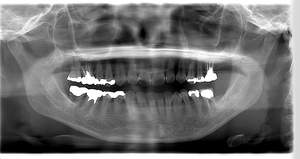

インプラント治療の症例1

レントゲン写真

- 透過像

| 年齢 | 50代・男性 |

|---|---|

| 主訴 | 右下歯が疼く |

| 治療内容 | ・右下6番インプラント ※1:FGG(遊離歯肉移植術)とは、足りない歯ぐきを上顎から上皮を切り取り移植する外科手術 |

| 治療費 | 合計:902,000円(税込) ■内訳 |

| 治療期間 | 9ヵ月 |

| 治療方針 | 右下の当該歯は歯根破折により保存不可能と診断しました。歯周疾患も伴っていたため抜歯後に骨吸収※1が大きく起こることが予測できました。チタンメッシュ併用骨再生誘導法(GBR※2)を選択しインプラント埋入と同時に行い自然な歯槽骨のラインを再現しました。またGBRを行う際にインプラント辺縁の付着歯肉の減少が起こる為、遊離歯肉移植術(FGG※3)を行い清掃性を考慮した形態に仕上げました。 ■治療方針の解説 治療した右下の歯をレントゲンで撮影したところ根本の部分に黒く写る箇所があり「根尖性慢性周囲炎※1」と診断。また歯周病も進行していました。 ※1 骨吸収・・・歯槽骨という歯を支える骨がなくなっていくこと |

| 担当者所見 | 主訴の右下だけでなく歯茎の腫れ、発赤があり不良補綴や不良充填など他にも治療箇所が多数ありました。プラークコントロールが不良であった為まずはブラッシング指導を行いセルフケアの重要性を理解していただくところからスタートしました。 右下6番の歯はインプラント治療を行なった結果審美的にも機能的にも患者様の満足を得ることができました。骨造成と歯肉移植も行なった為インプラントを支える十分な歯周組織の獲得ができたと思っております。 |